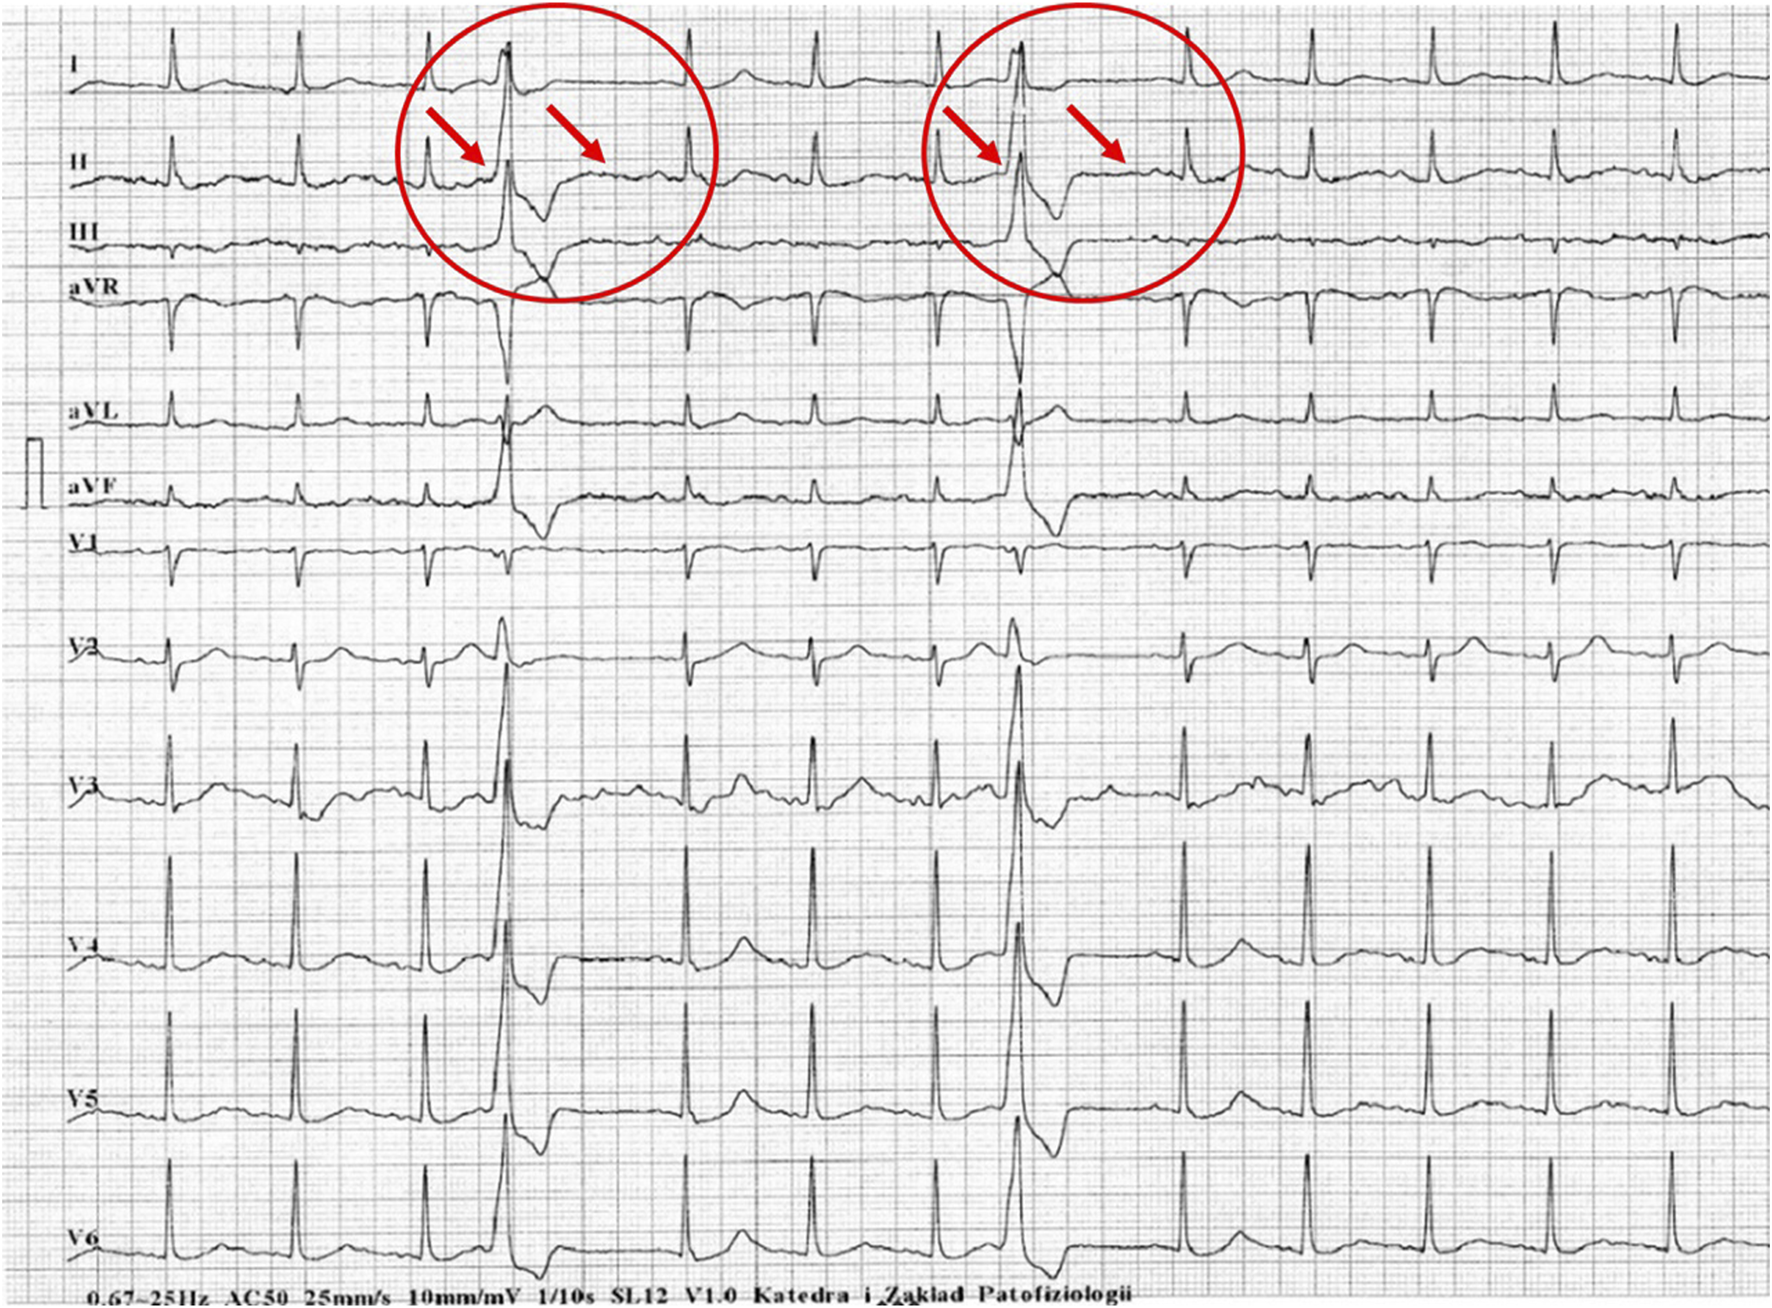

Figures 1–5 present a sample of ECGs incorrectly interpreted by the device. There are cases of pathologies commonly identified by clinicians. In Figure 1, we identified the dual-chamber pacing with a dual response (DDD) stimulation interpreted as atrial fibrillation and RBBB, so in this case, we have both overinterpretation and failure of recognition. A similar situation is presented in Figure 2, where we found the lack of atrial fibrillation diagnosis and at the same time overinterpretation with type 1 and 2 atrioventricular block. In Figure 3, the situation is presented where, instead of DDD pacing, LBBB and the atrial rhythm were proposed. Moreover, in Figure 4, the compensatory pause after premature ventricular beats was overinterpreted as atrioventricular Mobitz type II block. Finally, in Figure 5, we again identified the lack of proper diagnosis of the first-degree atrioventricular block, together with the overinterpretation of atrial fibrillation.

FIGURE 5

Example of incorrect interpretation by the device: Male, 78 years old. First-degree atrioventricular block described by the device as atrial fibrillation with intraventricular conduction block (25 mm/s, 10 mm/mV).